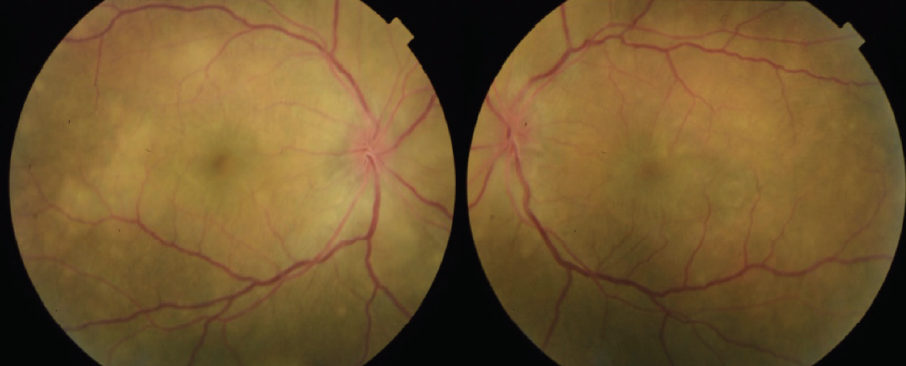

Figure 6. Color fundus photos 4 weeks after initiation of oral prednisone steroids demonstrate improvement.

The patient showed a robust initial response to steroids with significant improvement in her vision and anatomy. Within 1 week, her VA had improved to 20/100 OD and 20/70 OS. Fundus examination showed improvement with less defined lesions (Figure 4), and OCT showed significant reduction in fluid (Figure 5). After 1 month of treatment, her vision had improved to 20/50 OD and 20/40 OS, with further improvement seen on fundus findings (Figure 6) and near complete resolution of fluid on OCT (Figure 7). Continued improvement was seen 6 weeks after steroid therapy was initiated (Figure 8 and Figure 9). The marked improvement in structure and function with oral prednisone treatment, without ATT treatment, led to a presumed diagnosis of VKH disease.